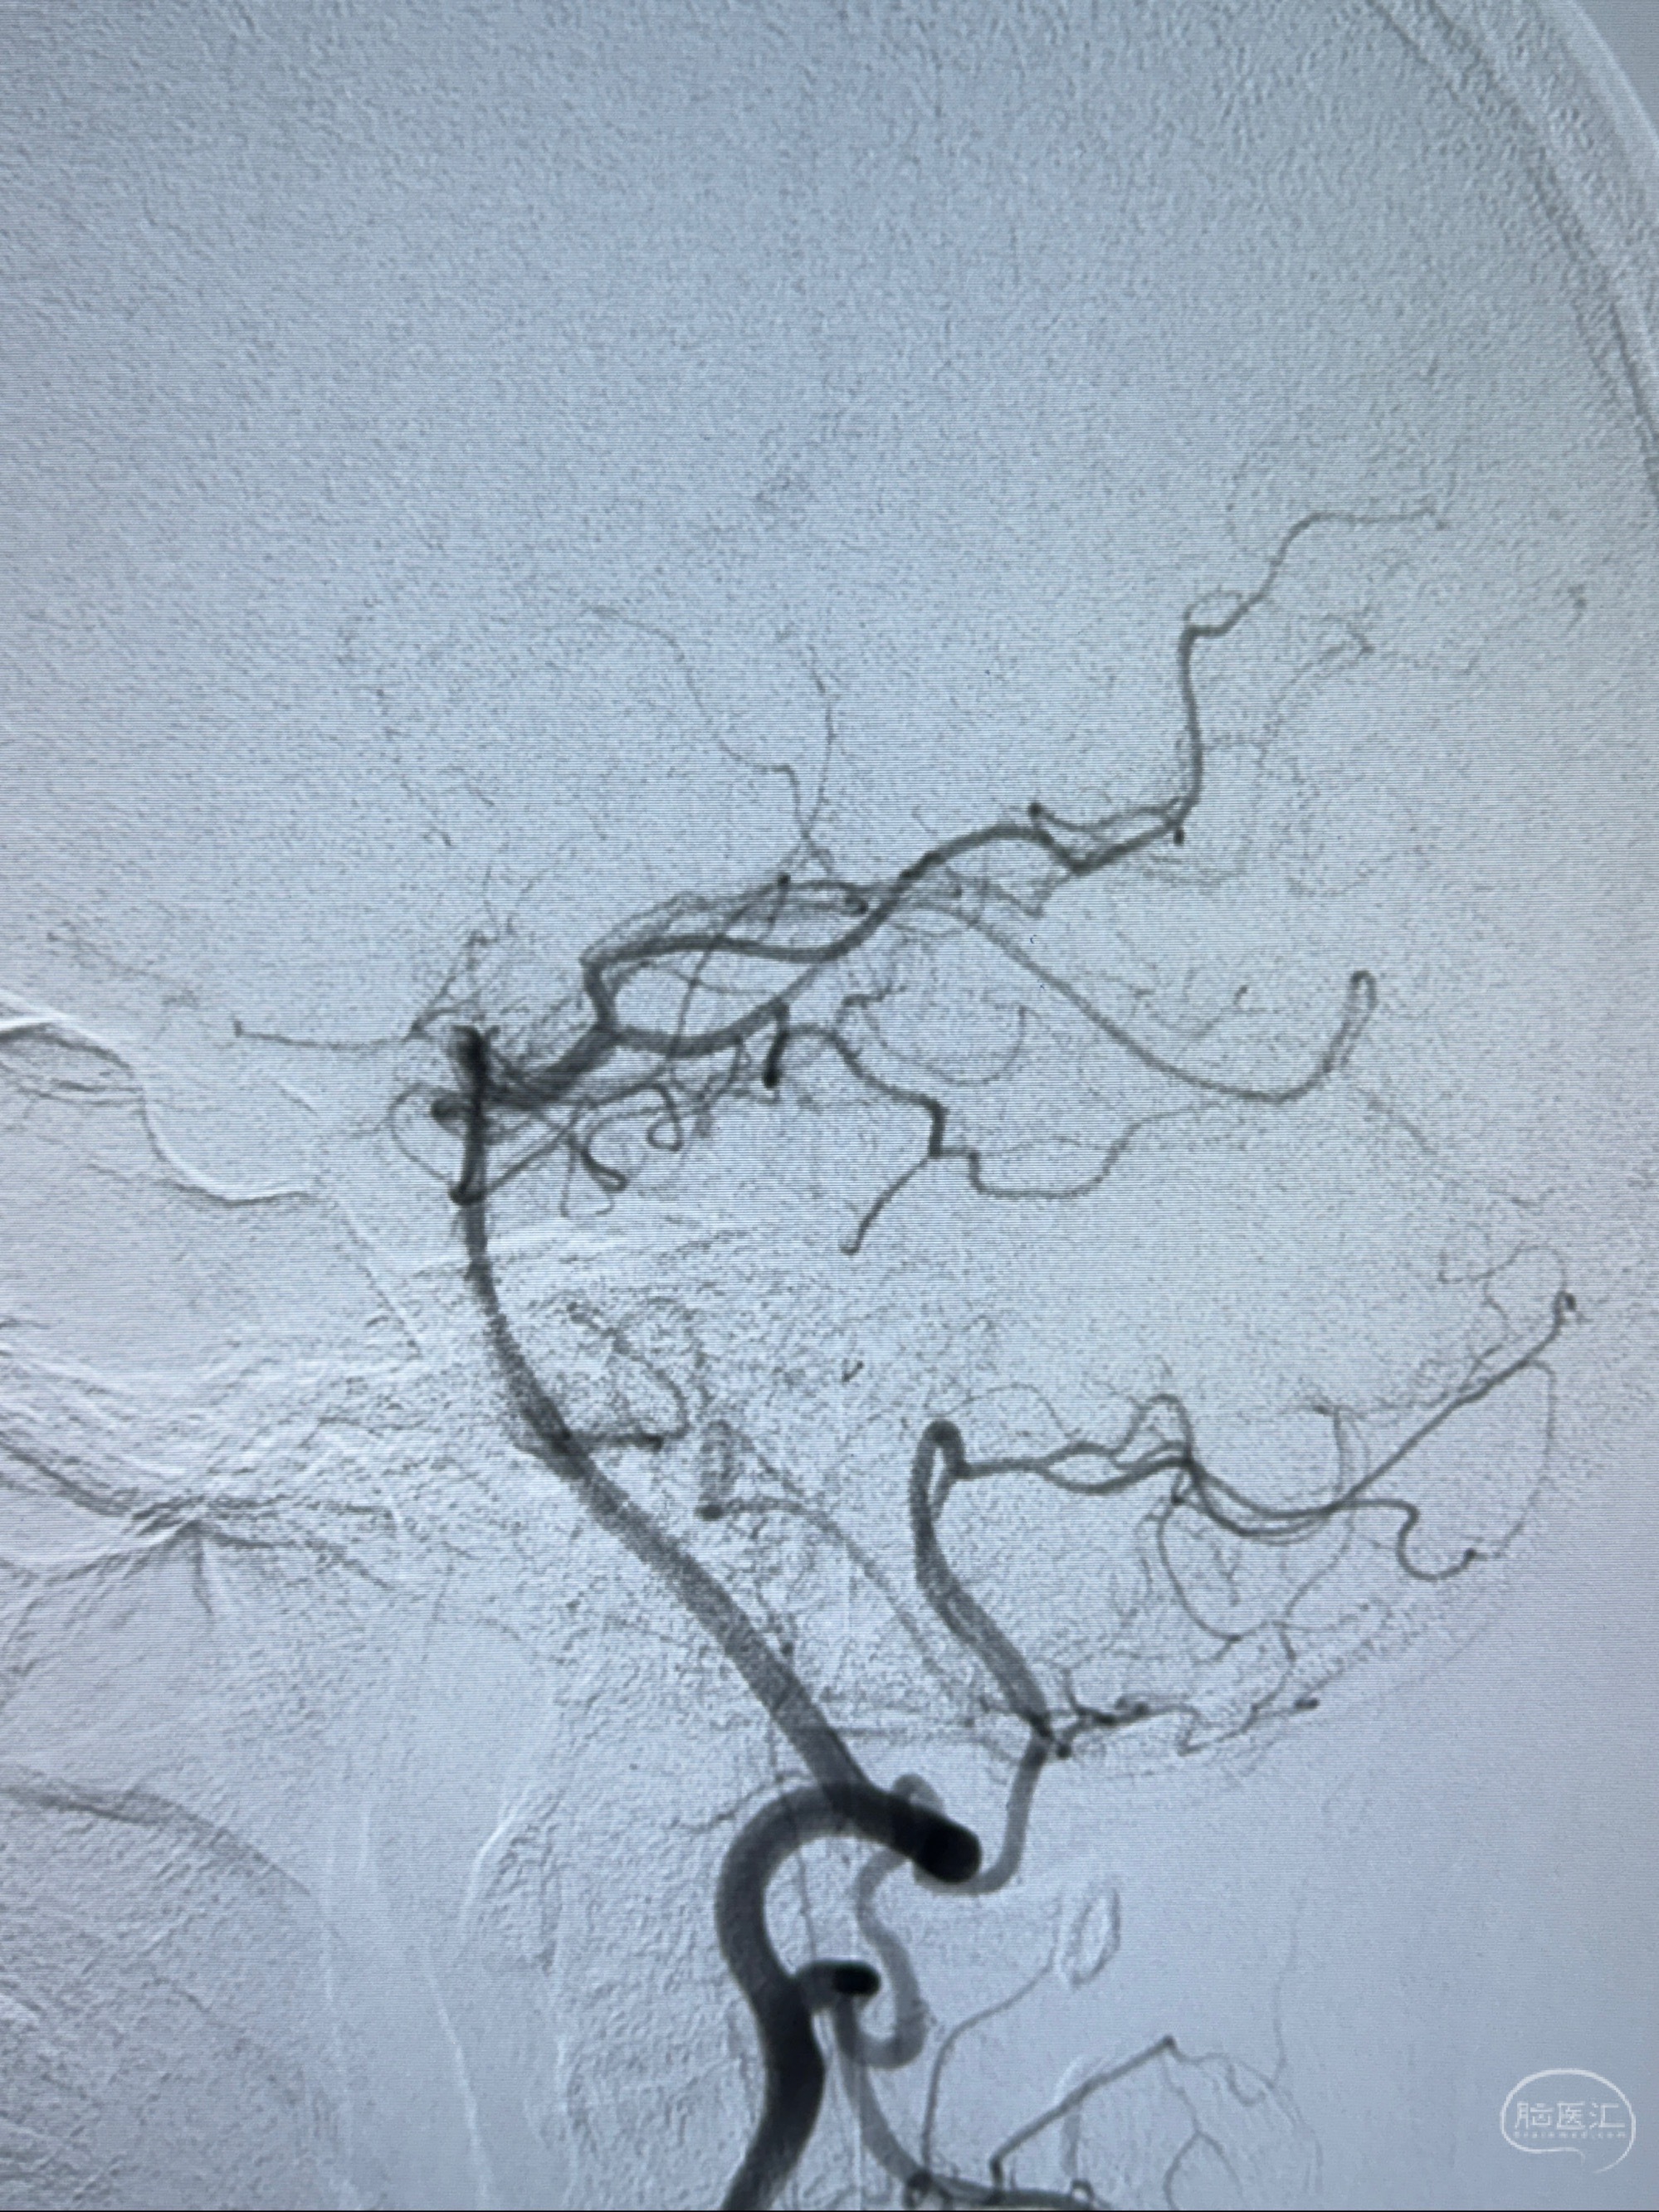

现病史:患者诉近4年来时有头痛发作,服用都梁软胶囊、氟桂利嗪对症治疗一月后症状改善,后头痛较少发作。近3月来患者头痛发作频率明显增加,约一月一次,为右侧偏头痛,胀痛,伴恶心呕吐,呕吐后症状可略减轻;遂于2023-11-01至蓝十字脑科医院就诊,查头颅MRI+DWI+MRA提示:左侧枕叶皮层下小斑片缺血或变性灶,右侧大脑前动脉A1段毛糙,显影淡、纤细,建议完善CTA;并于2023-11-03查头颅CTA提示:左侧颈内动脉C6段微小动脉瘤可能(约2mm),右侧大脑前动脉A1段纤细(对侧优势),左侧大脑中动脉提前分叉。现患者无明显不适,为求进一步诊疗颅内血管病变至我科就诊,收治入院。

2023-11-03 蓝十字脑科医院 头颅CTA:左侧颈内动脉C6段微小动脉瘤可能(约2mm),右侧大脑前动脉A1段纤细(对侧优势),左侧大脑中动脉提前分叉。

1.左侧颈内动脉瘤